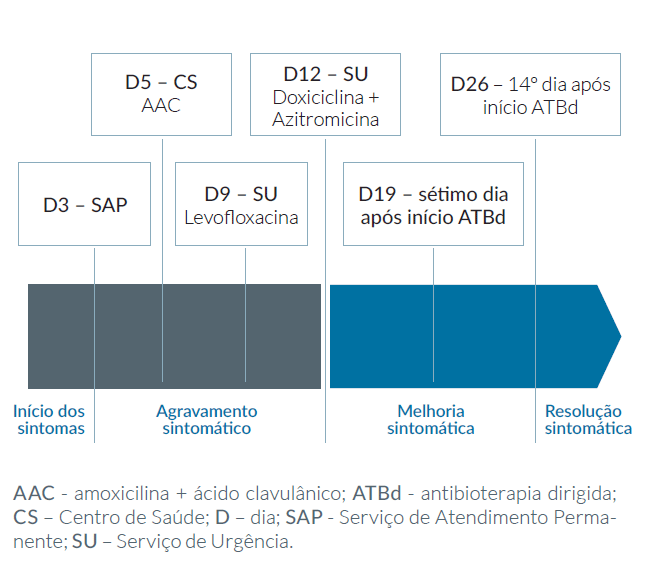

Foi observada num Serviço de Atendimento Permanente (SAP) por quadro de dispneia, tosse seca, toracalgia, cansaço generalizado e febre com três dias de evolução, tendo sido medicada sintomaticamente com paracetamol, tiocolquicosido e nimesulida. Não foi realizado qualquer meio complementar de diagnóstico (MCDT).

Por agravamento da sintomatologia, passados dois dias, foi novamente observada no Centro de Saúde (CS). Iniciou amoxicilina 875 mg + ácido clavulânico 125 mg, per os bi-diário (bid), e budesonida 160 μg/dose + formoterol 4,5 μg/dose, uma inalação bid.

Por manter agravamento progressivo do quadro clínico, apesar da terapêutica instituída, ao nono dia de doença e quinto dia de antibioterapia empírica dirigiu-se ao Serviço de Urgência (SU), onde realizou radiografia torácica, Fig. 1, que revelou “…opacidade na topografia do lobo superior direito, compatível com pneumonia lobar…” e análises clínicas cujos resultados estão na Tabela 1. Destaca-se marcada elevação da proteína C reativa (PCR) e das transaminases hepáticas. Realizou ainda ecografia abdominal que revelou “hepatomegalia homogénea com maior eixo de 22,5 cm. Sem outros achados dignos de referência”. Foi então medicada com levofloxacina 500 mg, per os de toma única diária (id), que cumpriu apenas 3 tomas por intolerância.

Apesar da terapêutica anterior instituída, a doente permaneceu sempre consideravelmente sintomática, com tosse seca, cansaço para as AVD´s e dispneia. Dirigiu-se então pela segunda vez ao SU, no 12º dia de doença, onde após uma anamnese mais detalhada foram pedidos os anticorpos anti-Chlamydia psittaci (IgG e IgM) que se revelaram ambos positivos. Foi então medicada com doxiciclina 100 mg, per os bid, durante 10 dias, e azitromicina 500 mg, per os id, durante três dias.

Foi reportada uma melhoria progressiva do quadro clínico, encontrando-se completamente assintomática após sete dias do início da terapêutica dirigida. Nas análises de reavaliação, duas semanas após o início da terapêutica dirigida, observam-se parâmetros inflamatórios e de função hepática em perfil descendente (Tabela 1), com melhoria sintomática significativa. Na Fig. 2 está representado o percurso e evolução clínica da doente.